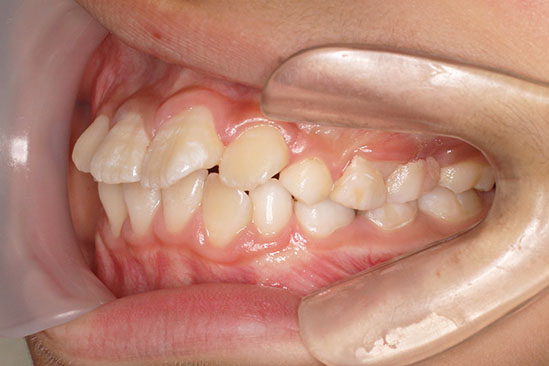

歯が重なっている、出っ歯を治したい 以前に治療した方からの紹介で来院した患者さんです。 上下顎前歯部の叢生(がたつき)、上下顎前歯の前方傾斜、 骨格的上顎前突傾向でした。 小児矯正で叢生の緩和を行い、 本格矯正で前方傾斜した前歯の改善を行いました。 マルチブラケット 動的治療期間 3年3か月 調整回数25回